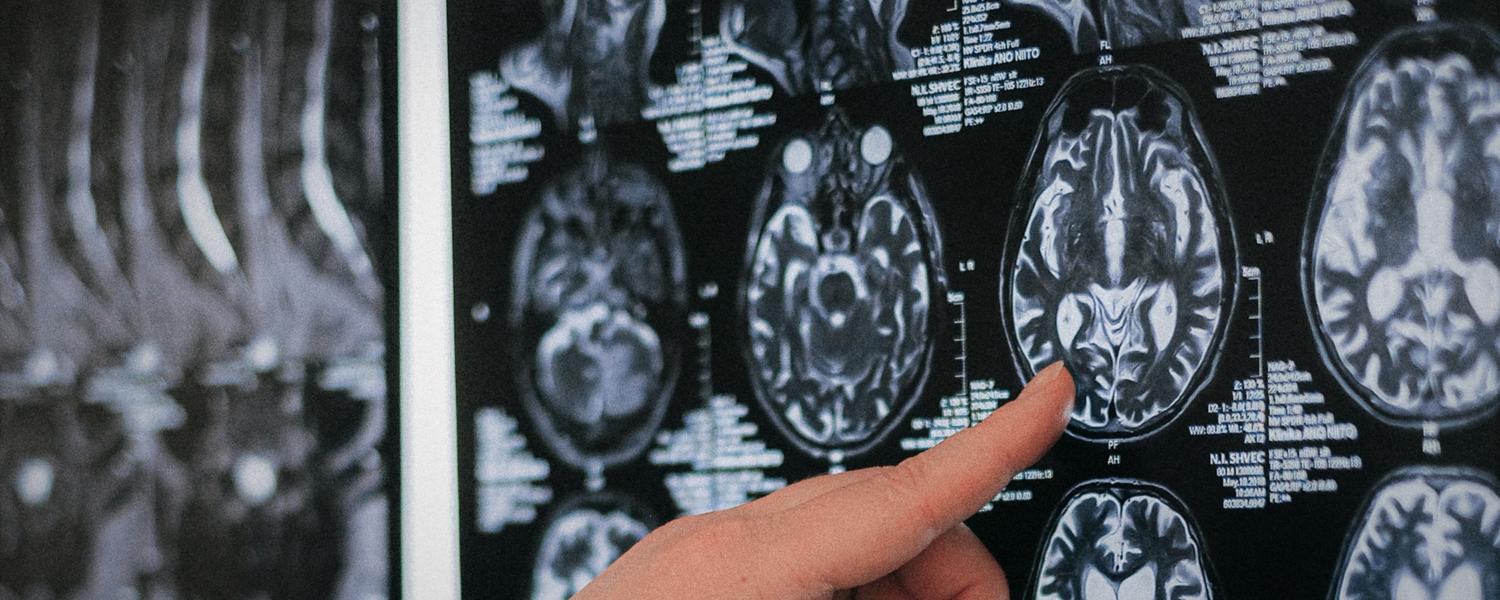

Fast and accurate automatic cerebrovascular segmentation is important for clinicians and researchers to analyze the vessels of the brain, determine criteria of normality, and identify and study cerebrovascular diseases. Nevertheless, automatic segmentation is challenging due to the complex shape, inhomogeneous intensity, and inter-person variability of normal and malformed vessels. The aim of this project is to develop automatic segmentation methods of the vessels of the brain in time-of-flight magnetic resonance angiography (TOF MRA) images.

Parkinsonian syndromes encompass a spectrum of neurodegenerative diseases, which can be classified into various subtypes. The differentiation of these subtypes is typically challenging. The aim of this project is to develop image-based classification methods of patients with Parkinson’s disease on diffusion-tensor magnetic resonance imaging (MRI).

Healthy brain aging leads to morphological changes in the cortical, subcortical and vascular structures of the brain. Several changes are also associated with neurological diseases such as Alzheimer’s diseases. Understanding better these changes is important to be able to differentiate pathological versus normal aging at an early stage.